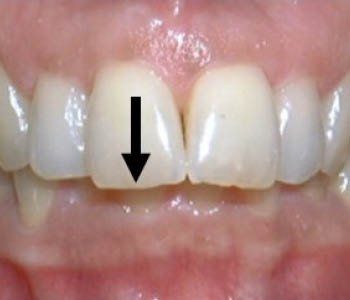

Diastema or Spacing

There is spaces or gaps between the teeth.